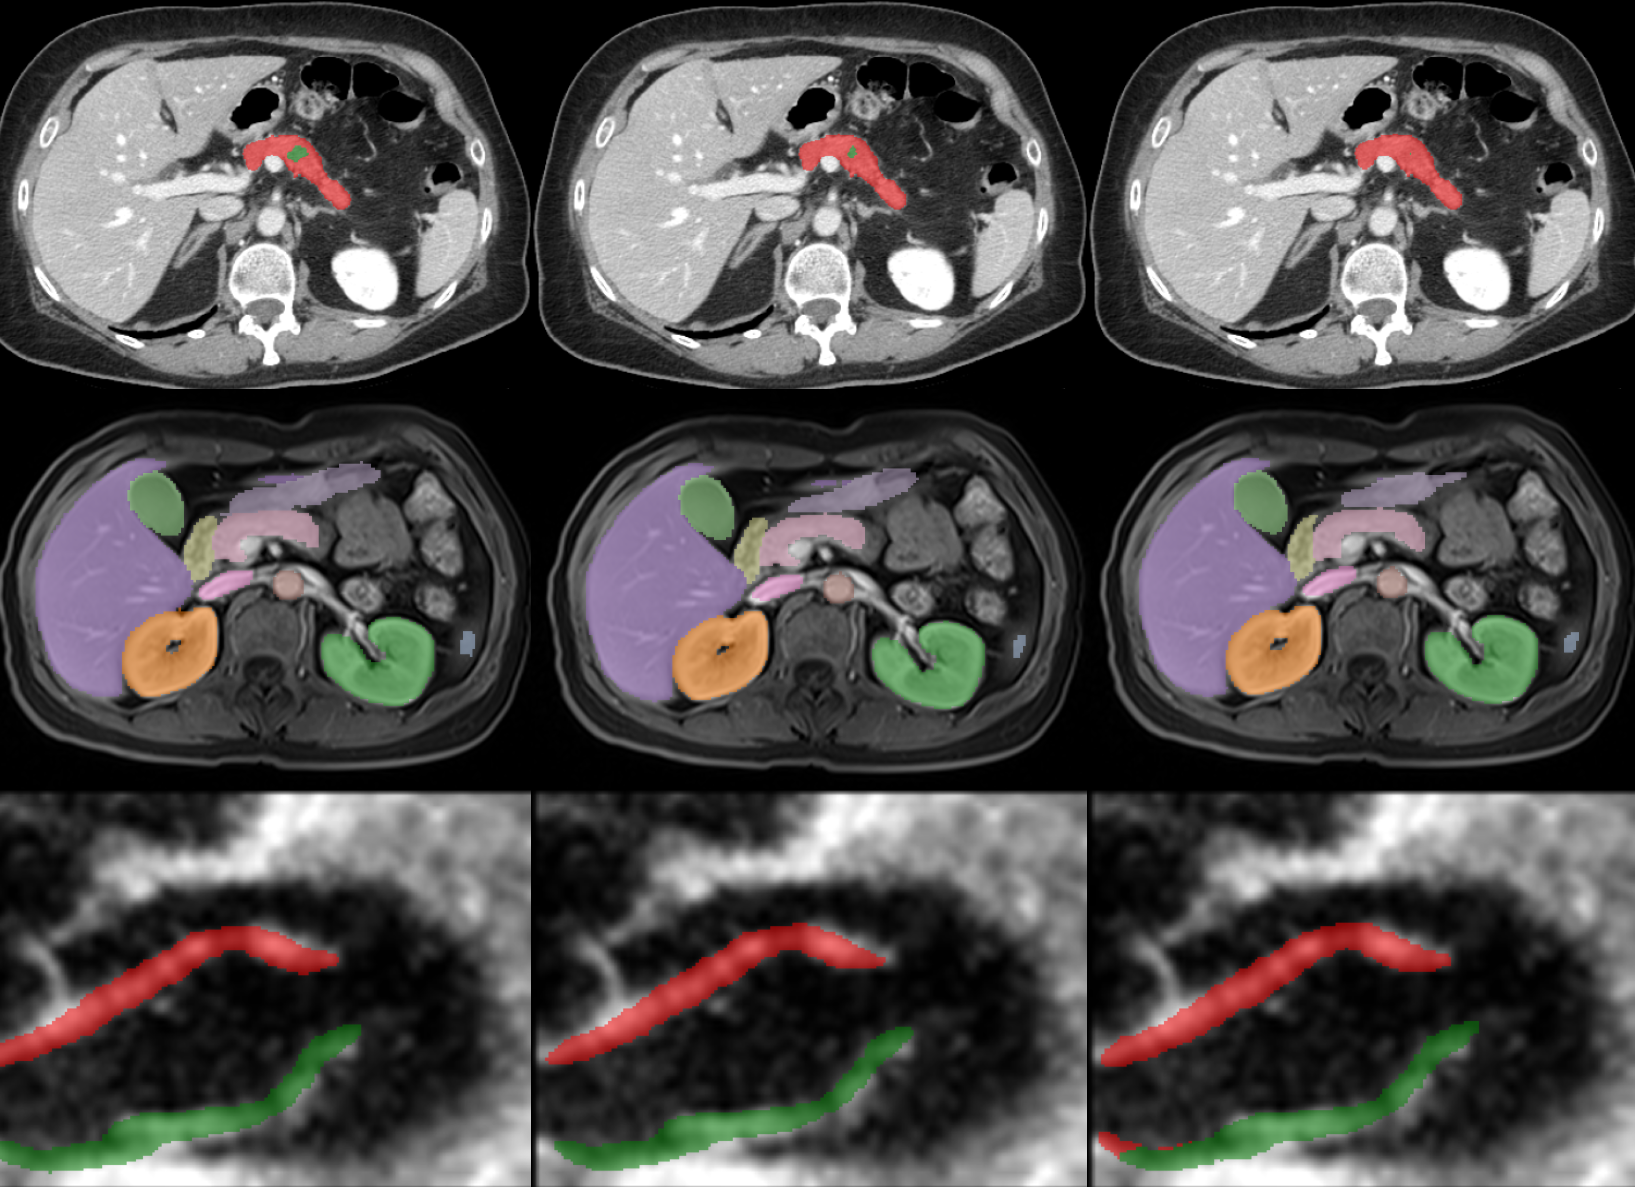

We introduce Hierarchical Soft Mixture-of-Experts (HoME), a novel two-level token-routing architecture for efficient 3D medical image segmentation across diverse modalities (CT, MRI, US). Built on the Mamba Selective State Space Model backbone, HoME addresses key challenges in medical imaging: modeling local-to-global spatial hierarchies, handling modality diversity, and achieving scalability for high-resolution 3D inputs. The architecture combines local expert routing with global context refinement through a hierarchical design that partitions sequences into groups, routes tokens to specialized experts for localized feature extraction, and aggregates outputs via a global layer for cross-group information fusion. Mamba-HoME demonstrates superior generalization and outperforms state-of-the-art models across multiple datasets while maintaining memory and computational efficiency.